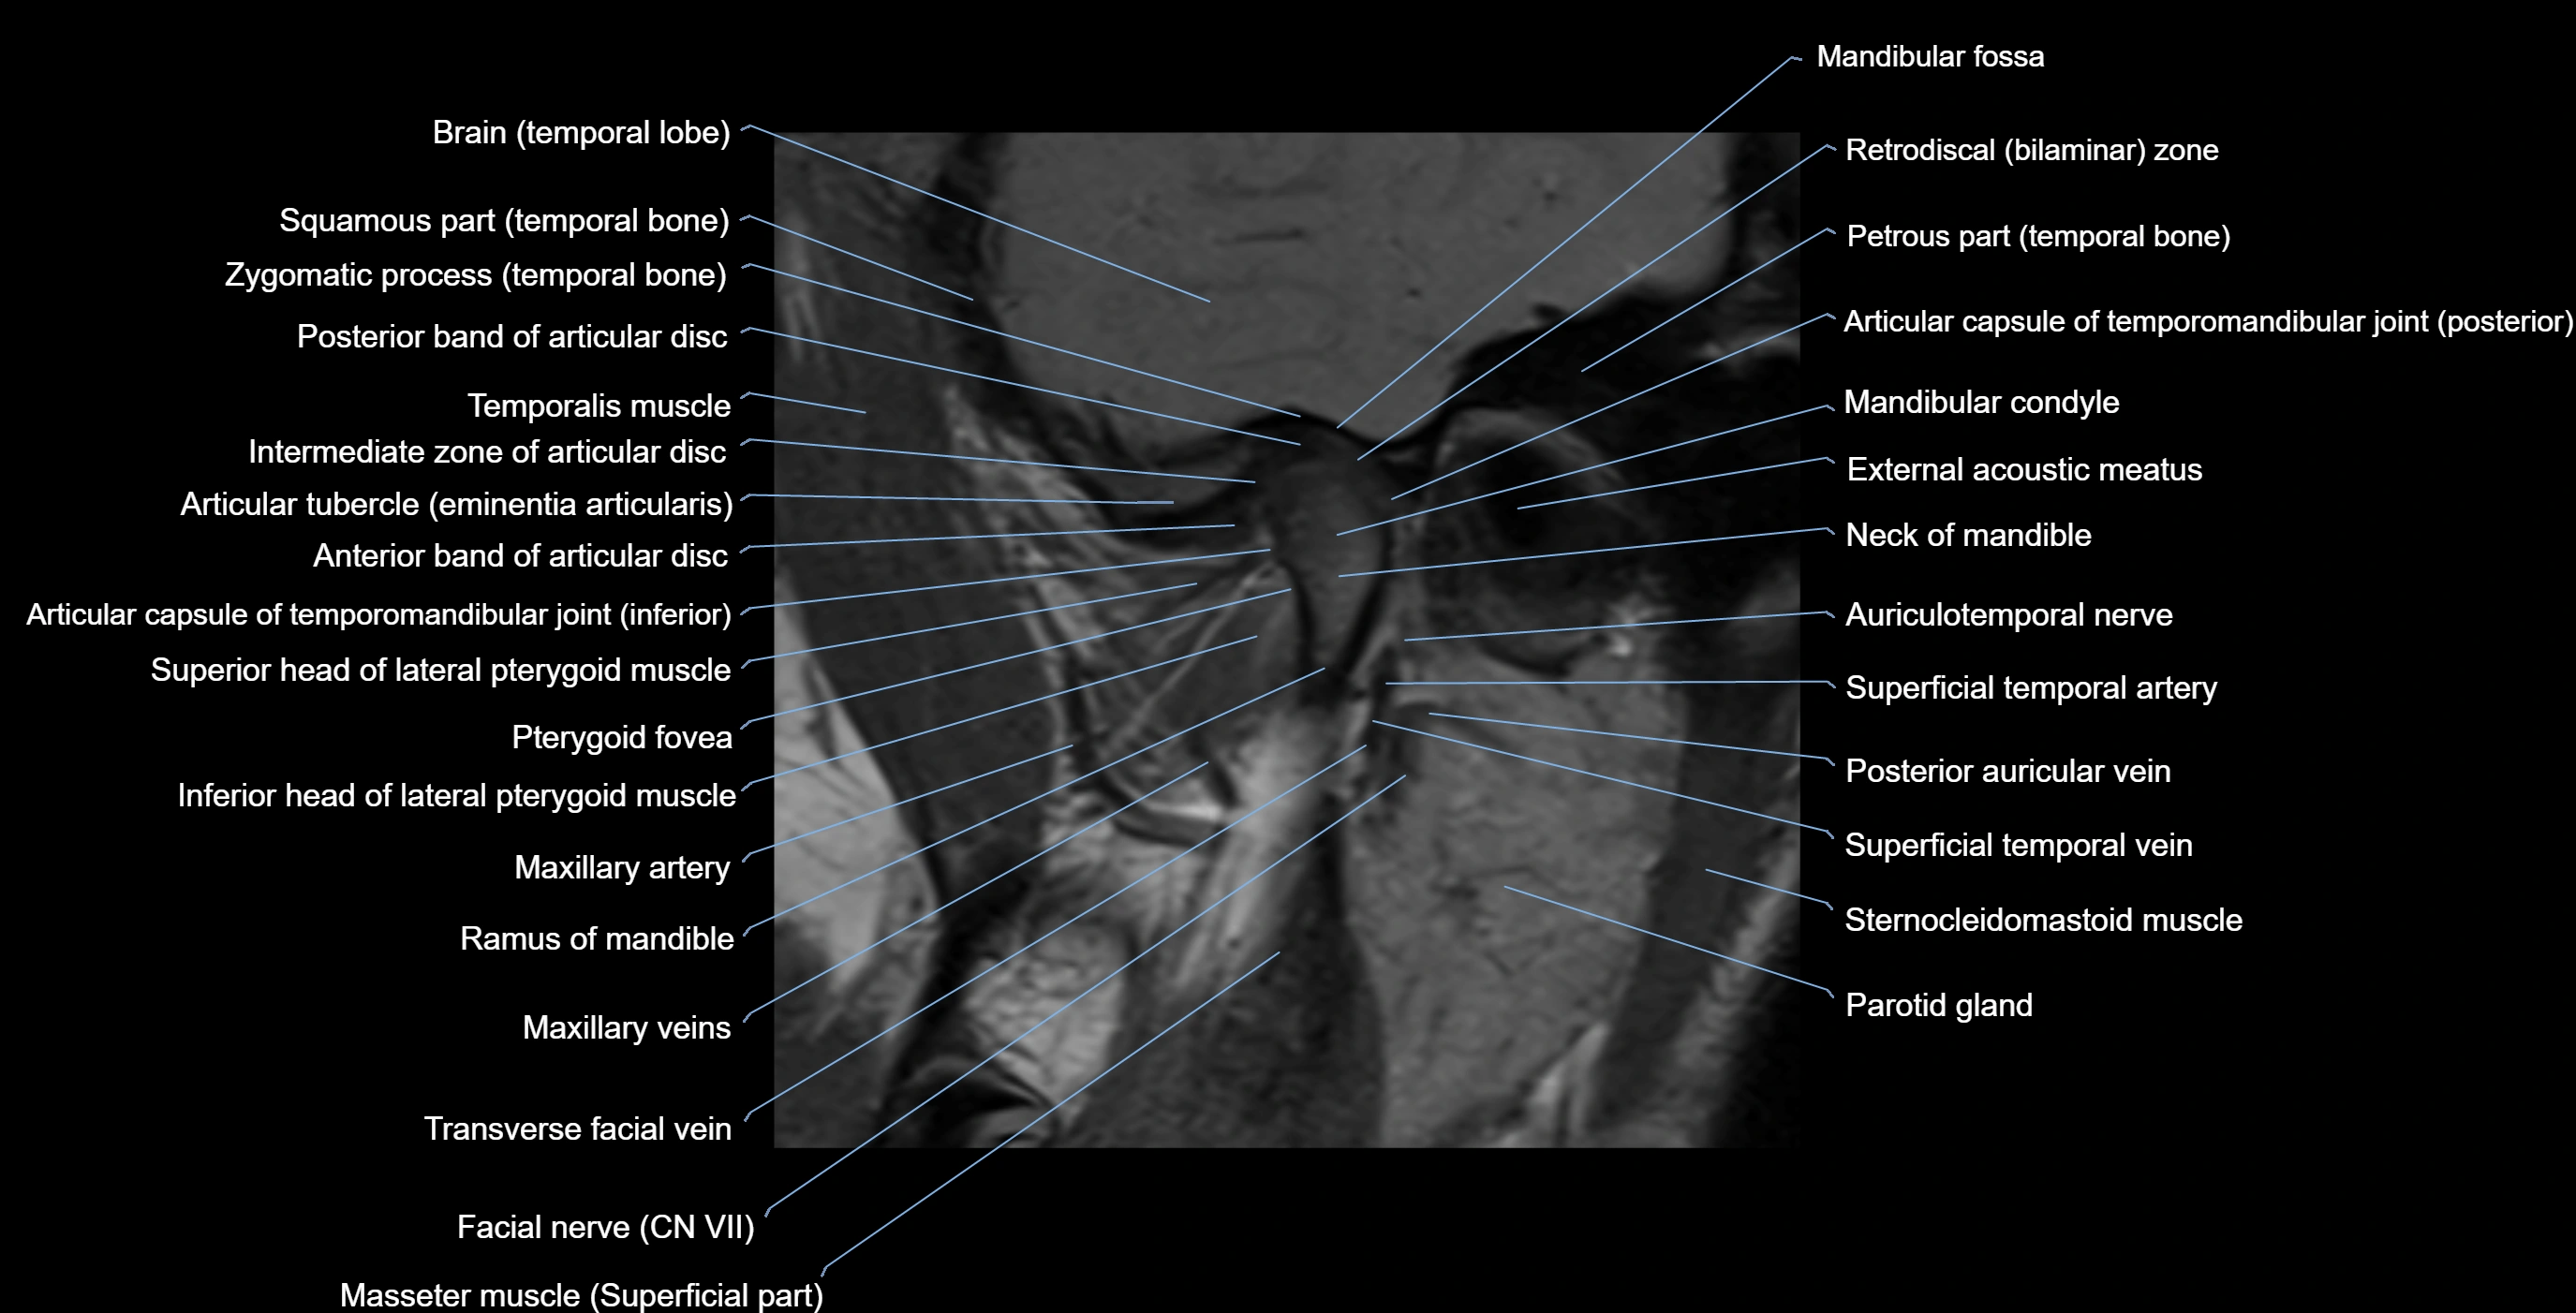

MRI appearance

T1-weighted images:

• Cortical bone: Low signal intensity

• Cancellous marrow: Intermediate to high signal depending on fatty content

• Teeth: Signal void structures

• Adjacent soft tissues: Normal gingiva and oral mucosa signal

T2-weighted images:

• Cortical bone and teeth: Low signal

• Marrow: Intermediate signal